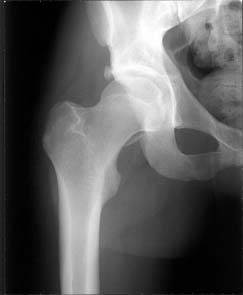

i'd like to see post reduction x-rays to assess congruency of the reduction including AP & both Judet views. If the fragment is truly small, and extra-articular and the joint is stable, probably nothing needs to be done with the fragment, but i'd like more views! thanks

Here are the missing postreduction views.